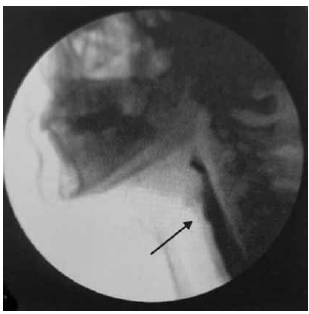

A Videofluoroscopia da Deglutição (VFD) possibilita a avaliação completa e dinâmica de todas as fases da deglutição, bem como apresenta grande sensibilidade e especificidade na detecção de aspiração. Observe a figura a seguir.

(Magalhães e Magnoni: Disfagia orofaríngea no adulto em ambiente hospitalar. Rubio, 2022. p. 81)

Assinale a alternativa que apresenta uma descrição compatível com o exame apresentado.